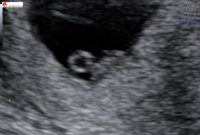

11+0❤️